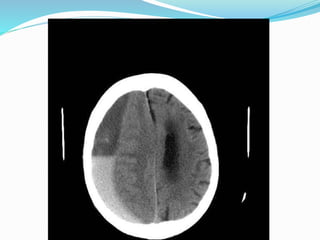

 CT Scan

 First diagnostic test

 The classic appearance of an acute subdural haematoma is a crescent shaped

homogeneously hyperdense extra axial collection

 Isodense in case of low HB

Specialized diagnosed evaluation X ray skull  CT Scan  First diagnostic test  The classic appearance of an acute subdural haematoma is a crescent shaped homogeneously hyperdense extra axial collection  Isodense in case of low HB  MRI  More sensitive & specifiec than CT scan